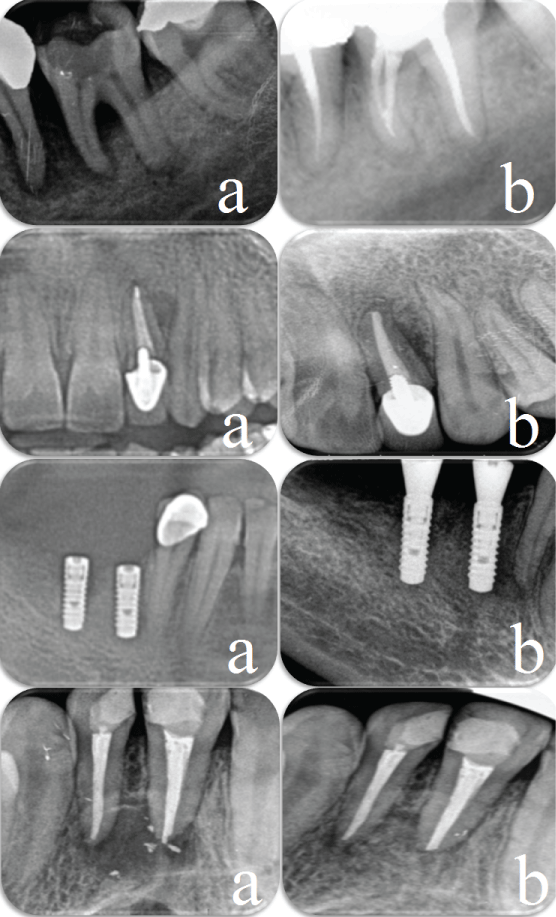

At 1-week post-surgical follow-up the sutures were removed. The patients experienced mild postoperative pain and swelling. There were no significant complications, such as bleeding, severe pain, or delayed wound healing. Clinical healing was uneventful, with neither infectious episodes nor untoward clinical symptoms. Recall radiographs of cases at 3 months showed satisfactory healing of the bony defects (Figure 2). The patients were also satisfied with outcomes of the treatments.

Figure 2: a) Pretreatment radiographic views showing bone defects; b) Periapical radiographic view 3 months after surgery showing evidence of bone healing.